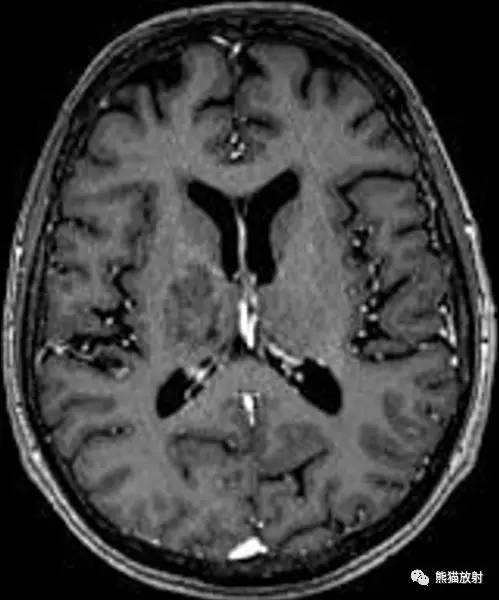

影像学表现

CT:皮质下和侧脑室周围白质密度减低,但无占位效应。

MRI:皮层下白质和深部白质见多发 T2 高信号,为斑片状神经脱髓鞘,灰质受累常见于病变晚期。病变有向额叶、顶枕叶、丘脑和基底核侵犯的倾向,有时也可以累及脑干和小脑。强化和占位效应少见,可单发、多发或者广泛侵犯,很少累及皮层下弓形纤维,不过多出现磁敏感伪影。